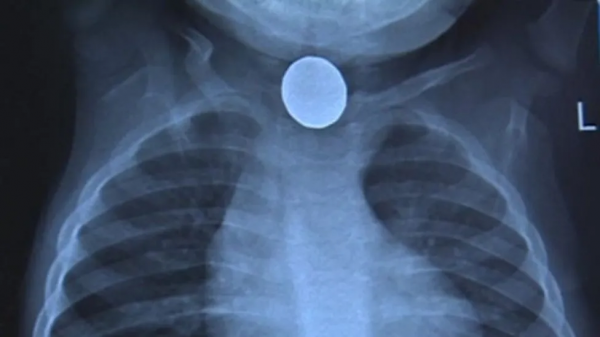

誤吞電池,心臟燒出一個洞

原來,一顆小小的紐扣電池,死死地卡在了休伊的食道里,導致他的心臟燒出了一個硬幣大小的洞,並且他的其他內臟也出現了不同程度的損傷,尤其是肺部衰竭十分嚴重。